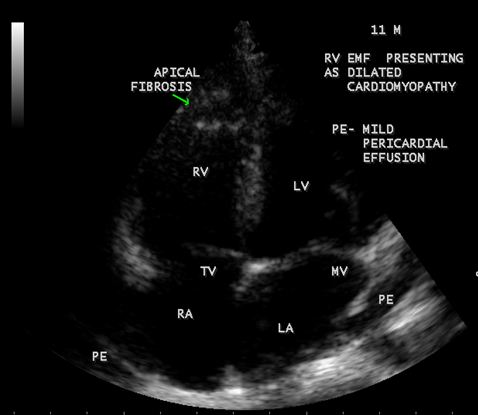

Figure 37: Endomyocardial fibrosis presented with dilated cardiomyopathy with RV apical fibrosis in a 11- year old male child.

Endomyocardial Fibrosis may present as dilated cardiomyopathy in a child as shown in Figure 37 [34]. In some cases, scattered areas of fibrosis in the submitral and subtricuspid regions may cause valvular regurgitation as shown in Figure 42. The valvular regurgitations occur in rheumatic heart disease and the differential features are given in Table 2. It may coexist with RHD (rheumatic heart disease) rarely as shown in Figures 27 and 28 [35].

Today echocardiography is used as the screening tool at the community level as the diagnosis of EMF could be confirmed at the bedside. Echocardiography accurately assesses the pathological abnormalities of chronic disease and it is the gold standard technique for the diagnosis of EMF [36]. It reveals dense endomyocardial echocardiograms along different parts of the mural and valvular endocardium and AV valve dysfunction [37] as shown in Figures 3 to 44. The typical feature of EMF is the obliteration of trabecular portion of the ventricle and in advanced cases, there is shrinkage of the cavities creating an apical notch, regurgitation, slow flow with spontaneous echo contrast as in Figure 36 and considerable pericardial effusion. Similar to apical notch of right ventricle, a right atrial notch is well seen as contraction (or retraction) of tricuspid annulus as in Figure 40 and right atrial notch as in Figure 41 and 42, indicating the retraction of rightatrial cavity as a peculiar feature of right ventricular EMF. Biventricular enlargement as shown in Figure 40 and biatrial enlargement as in Figure 32 are the characteristic features of advanced stage of EMF. The fibrosed muscular trabeculae extending into the cavities from the walls of the chambers in the right ventricle visible as ‘cobra heads’ as in Figure 4 and in pericardial sac as in Figure 29, in the left ventricle. Aneurysmal right ventricle with scattered areas of fibrosis in the sub tricuspid region and a notch in the right atrium is well seen in a 14 –year old boy as in Figure 42 . Right atrial notch is frequently noticed in EMF patients as shown in Figure 41 in a 47- year old male with left ventricular EMF and moderate pericardial effusion.